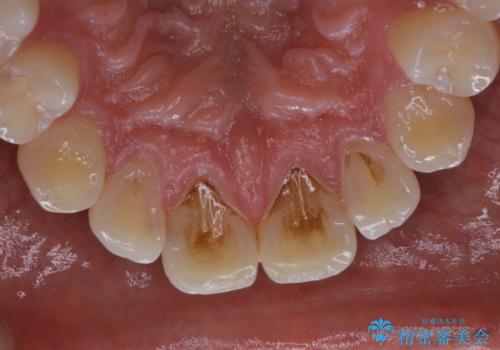

コーヒーの着色が前歯について目立つ

- コーヒーを毎日飲むので、どうしても着色がついてしまう。前歯の目立つ着色をきれいにとってほしいとのことでした。